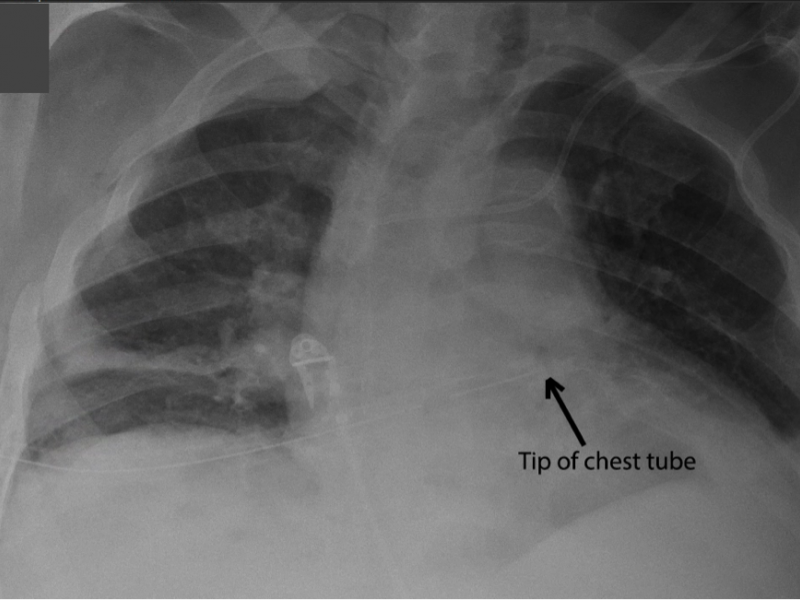

Back to Basics:  Chest Tube Insertion

Tricks of the Trade for Inserting a Surgical Chest Tube